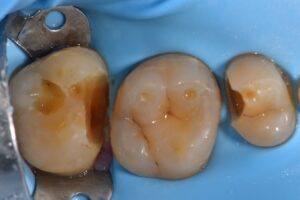

October 13, 2025 Direct Restoration #ClamplessDME #GarrisonCompositight #MajestyES2Universal Previous Post Next Post